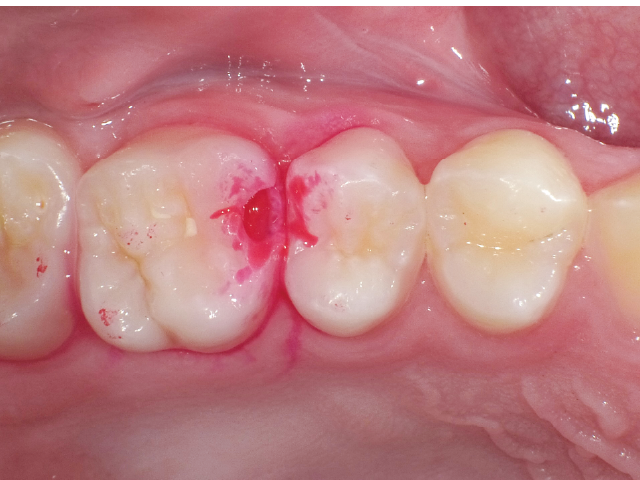

本稿では、最小限の健全歯質除去でう窩の開拡を行い、う蝕検知液を併用して感染象牙質に限定したう蝕除去を徹底し、最終的には隣在歯の誤切削防止が可能なエアースケーラーチップにより窩洞形成を仕上げた症例を示しながら、いかにして今日求められるMI修復を実現していくべきかを提示していきます。

①窩洞形成段階(図1~7)

本症例では、ダイヤモンドの微粒子でコーティングされたエアースケーラーチップを窩洞形態の仕上げに使用。隣在歯の誤切削を防止し、エナメル質の切削断面を歯肉側窩縁までなめらかになるよう仕上げました。